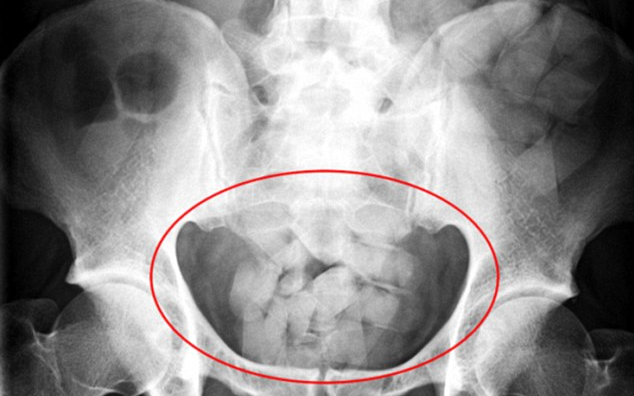

Mintegy 13 millió forint értékű kokainnal a gyomrában próbált meg bejutni az országba egy venezuelai nő, akit a NAV pénzügyőrei feltartóztattak a Liszt Ferenc-repülőtéren - közölte a NAV hétfőn az MTI-vel.

A közlemény szerint a budapesti repülőtérre egy Zürichen keresztül Sao Paulóból érkező venezuelai állampolgárt ellenőriztek a pénzügyőrök. Az utas a zöldfolyosón jelentkezett belépésre, azaz nem jelentett be semmilyen árut vámkezelésre, de az átvizsgálás során izzadt és remegett, így a pénzügyőrök feltételezték, hogy "kábítószernyelővel" van dolguk. A NAV munkatársai CT-vizsgálatra vitték, így derült ki, hogy a gyomrában 76 kapszulában 673 gramm kokain volt.